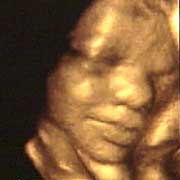

圖文:胎兒子宮內(nèi)表情豐富 專家稱提供研究新依據(jù)

中新網(wǎng)9月13日電 英國天空新聞報道,英國科學(xué)家圖亞特·坎貝爾最近利用先進(jìn)的掃描技術(shù)清晰地拍下了孕婦子宮中胎兒的表情,透過他拍攝的照片,人們可以清楚的看到一個尚未降臨世間的小生命喜、怒、哀、樂的表情。

斯圖亞特.坎貝爾是倫敦著名的產(chǎn)科教授,他利用超聲掃描技術(shù)拍攝到了胎兒在子宮中打呵欠、眨眼、吮手指、哭泣甚至微笑的畫面,這些都為胎兒行為的研究提供了新的依據(jù),專家認(rèn)為,這一突破將推動嬰兒健康科學(xué)的發(fā)展,包括對唐氏綜合癥等嬰幼兒疾病的診治將起到極大的推動作用。

此前,醫(yī)學(xué)界一直認(rèn)為,嬰兒要到降生后才可以做出喜、怒、哀、樂的表情,要通過模仿母親才可以學(xué)會微笑。

坎貝爾教授說:“有個這種技術(shù),現(xiàn)在許多問題都可以進(jìn)行研究了。比如說,患有唐氏綜合癥的嬰兒和正常嬰兒的活動方式是否一樣?胎兒是否因為高興才笑?胎兒哭是否是因為在子宮中受到打擾?既然我們都認(rèn)為子宮內(nèi)是一片黑暗,那胎兒為什么會眨眼呢?”(章田)